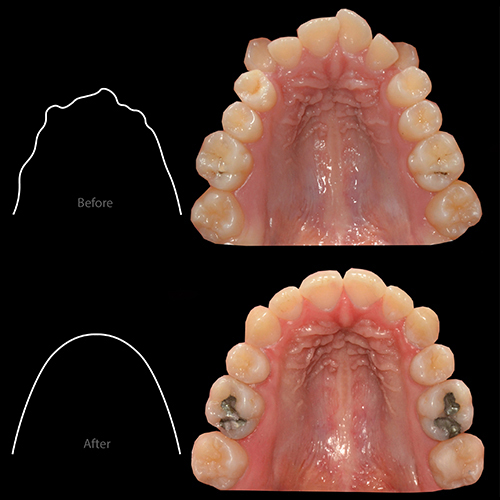

- تنگی نسبتاً شدید فک بالا

به علت کمبود فضای شدید در هر دو فک بیمار و نیز نهفتگی بسیار شدید دندانهای عقل، طرح درمان انتخاب شده برای بیمار، کشیدن دندانهای پرمولر اول در هر دو فک اعمال شد.

جهت جلوگیری از تأثیرات نامطلوب کشیدن دندان بر روی بافت نرم بیمار به خصوص حالت لبها به واسطه تکنیکهای کنترل بستن فضای دندانهای کشیده شده تنها ۶۰ ٪ از فضای دندانهای کشیده شده جهت چیدمان دندانهای قدامی استفاده شد و مابقی فضا از طریق حرکت رو به جلوی دندانهای خلفی بسته شد.

تنگی فک بالا با استفاده از تکنیک MEAW در فک بالا درمان شد. لازم به ذکر است به دلیل استفاده از این تکنیک در کمترین زمان ممکن (۲ ماه) عریض شدن فک بالا بدون ایجاد Buccal Flaring دندانهای خلفی میسر شد.

- افزایش نمایش و پر شدن لبخند به دلیل افزایش عرضی فک و چیدمان دندانها در قوس فکی عریضتر

- عریض شدن بیس فکی